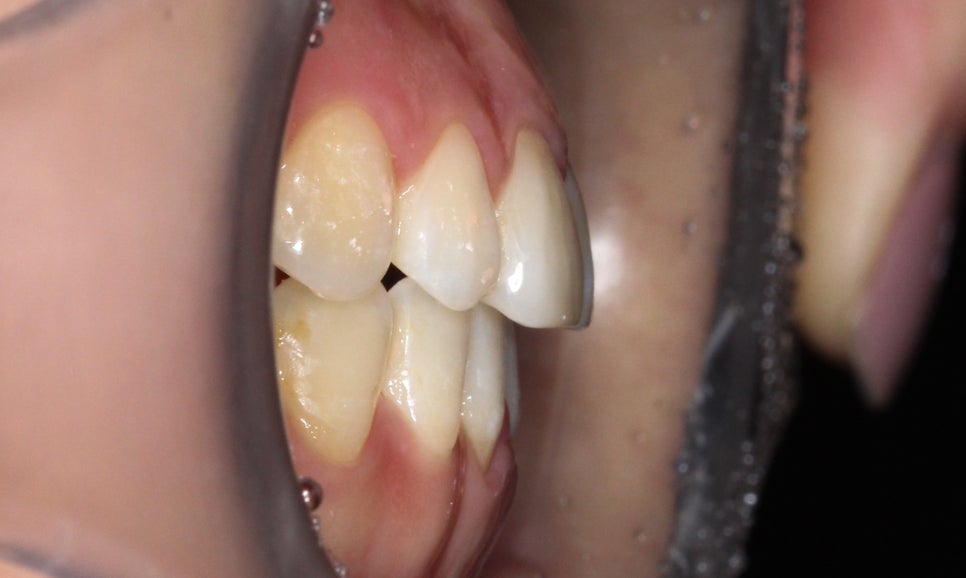

절단교합 교정 전 구내 사진입니다.

전치부를 보면 상악과 하악이

교합되는 부분에서 치아가 맞닿아 있는 모습인데요,

정상적인 교합 상태의 경우 상악이

하악의 윗면을 2mm정도 덮도록 교합됩니다.

(정중선도 변위되어 있는 모습)

증상을 더 자세하게 살펴보면

전치부 overbite 수치가 0에 가까운 모습으로

상악과 하악의 겹쳐지는 부분이 없습니다.